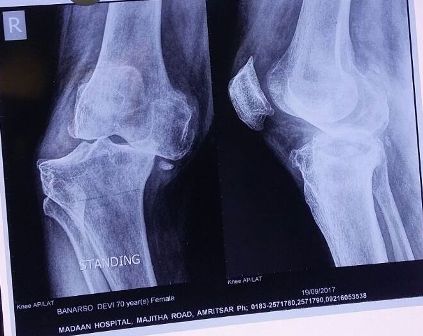

Patient : Mrs. Banarso Devi

Age / Sex : 71 yrs Female

• Old age patient with Ligamentous Instability.

• Not able to bear weight from last 5 years.

• Walk with walker without weight bearing with flail knee.